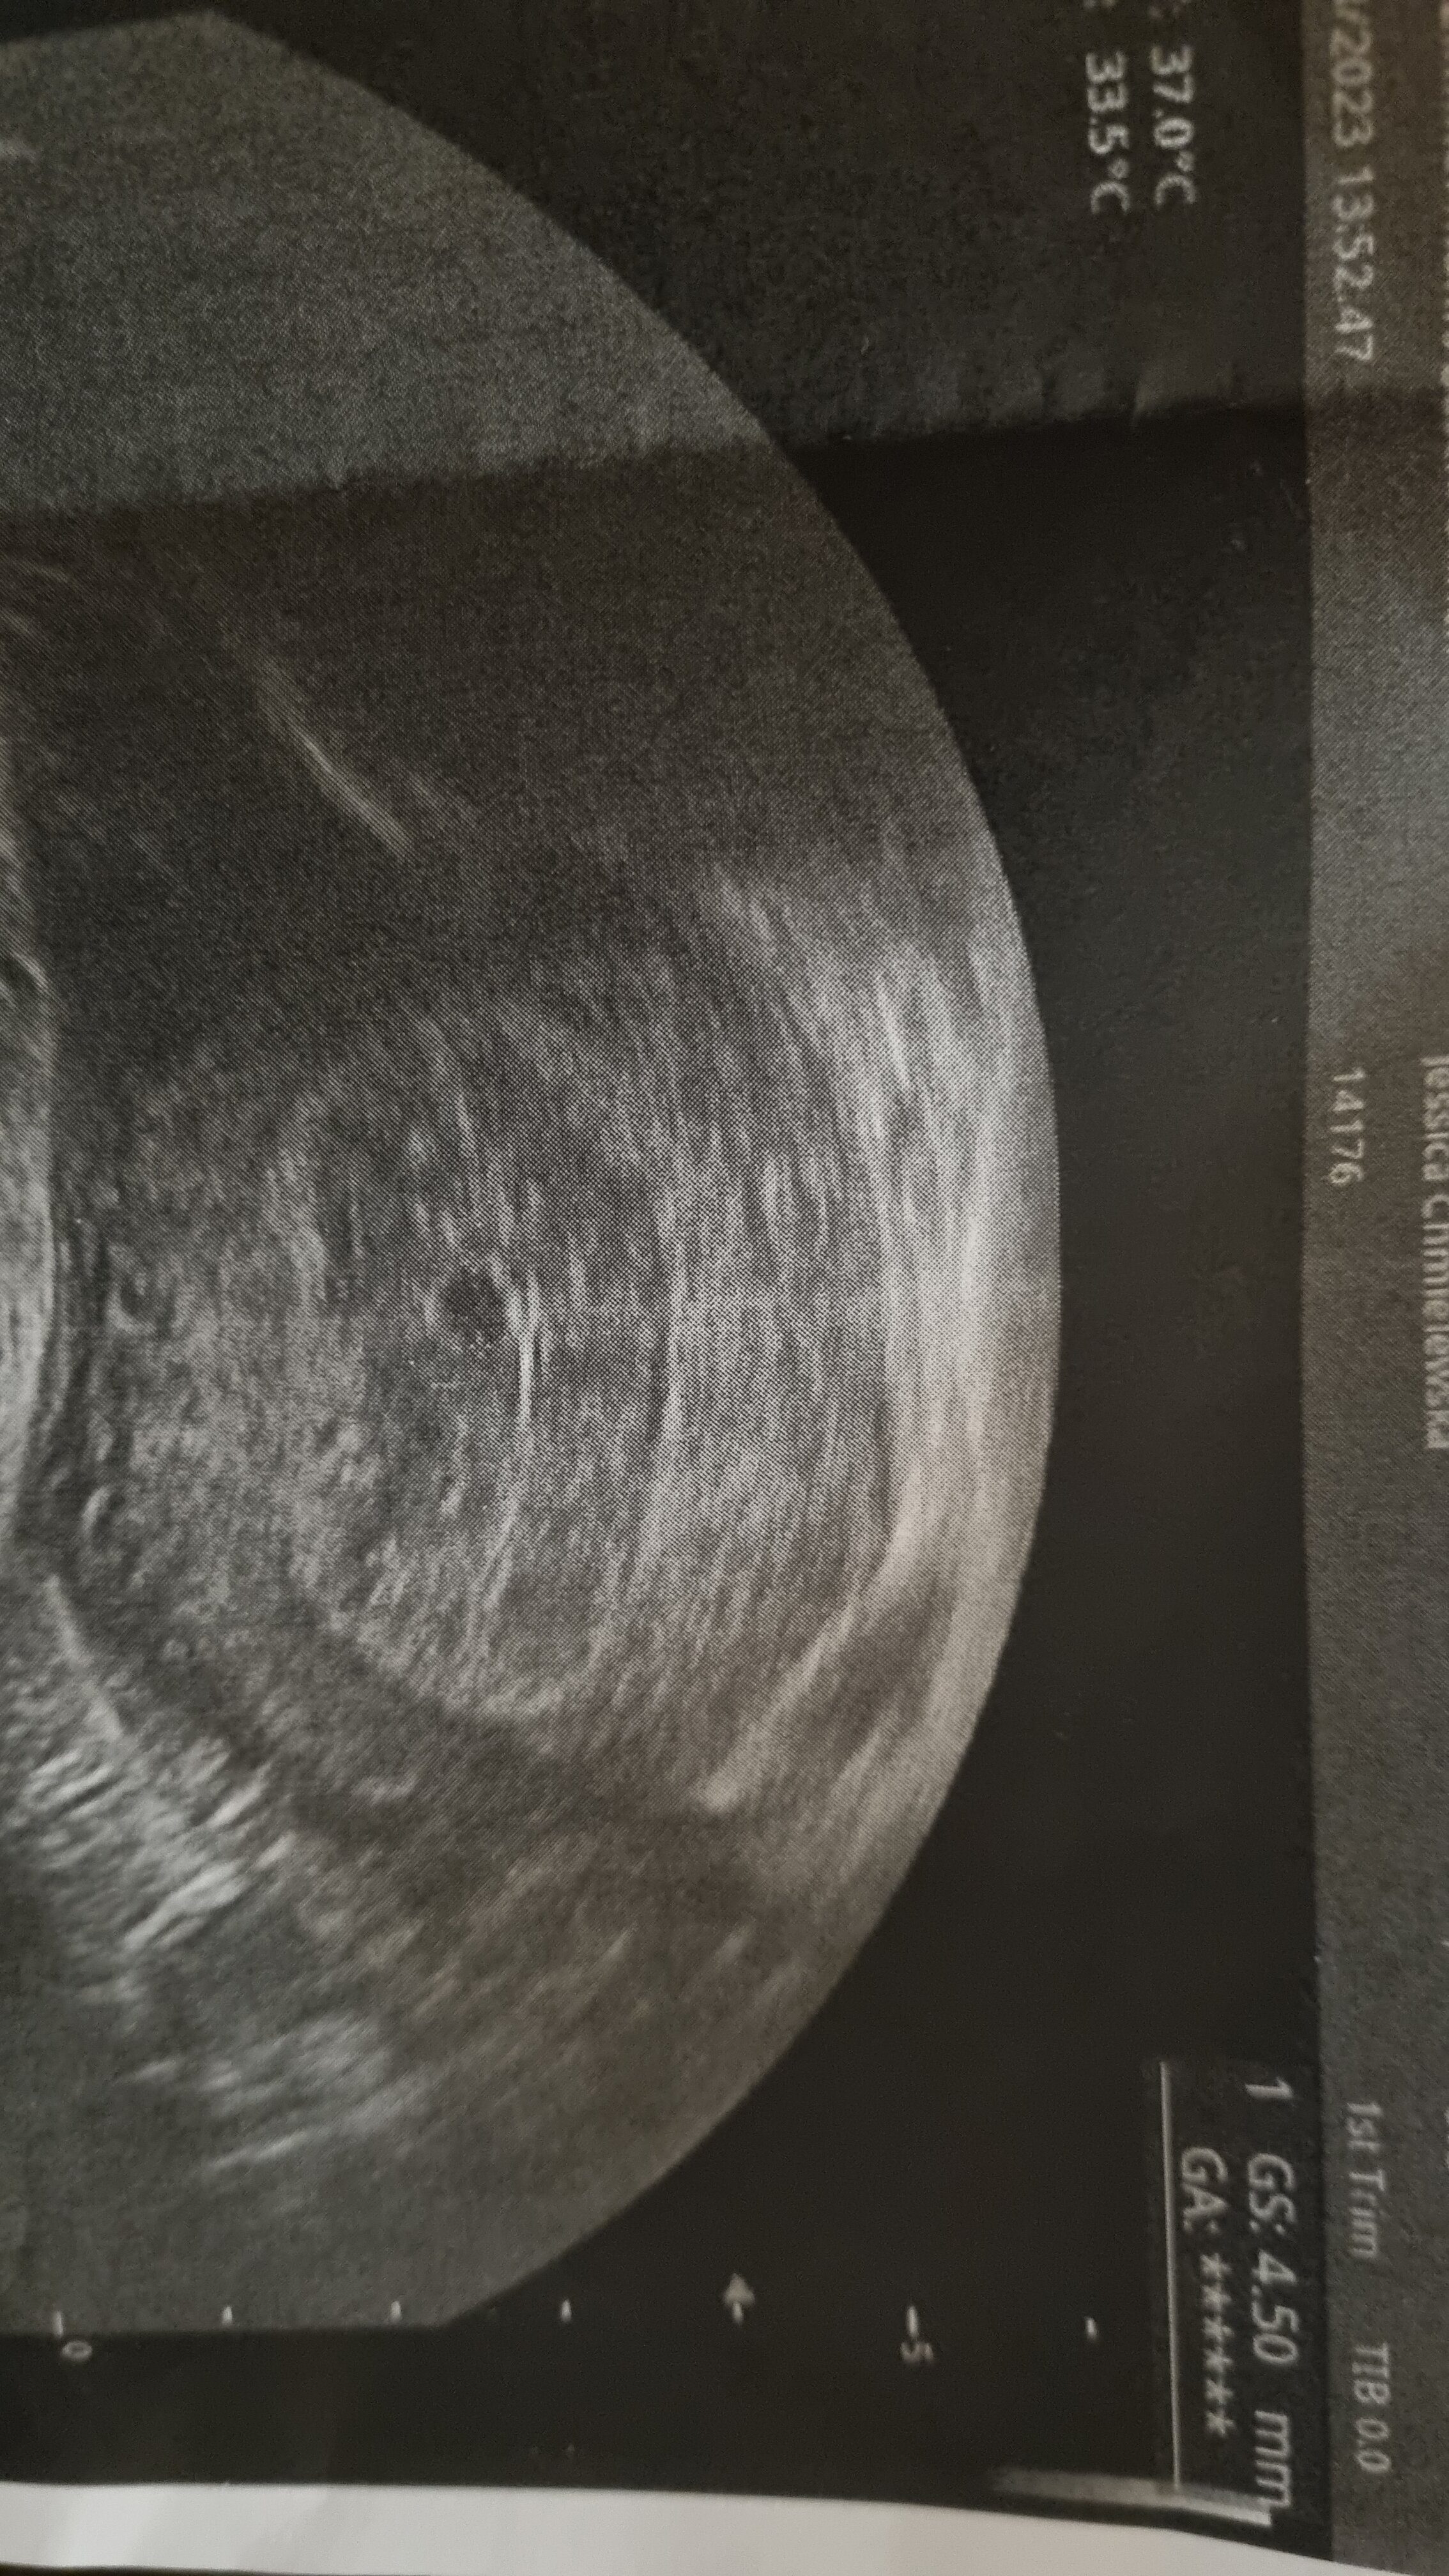

Przy tak niskiej becie ciężko go dojrzeć. Dopiero koło 1000 można go uwidocznić.Nie mógł widzieć pęcherzyka w takiej sytuacji?

Przy tak niskiej becie ciężko go dojrzeć. Dopiero koło 1000 można go uwidocznić.